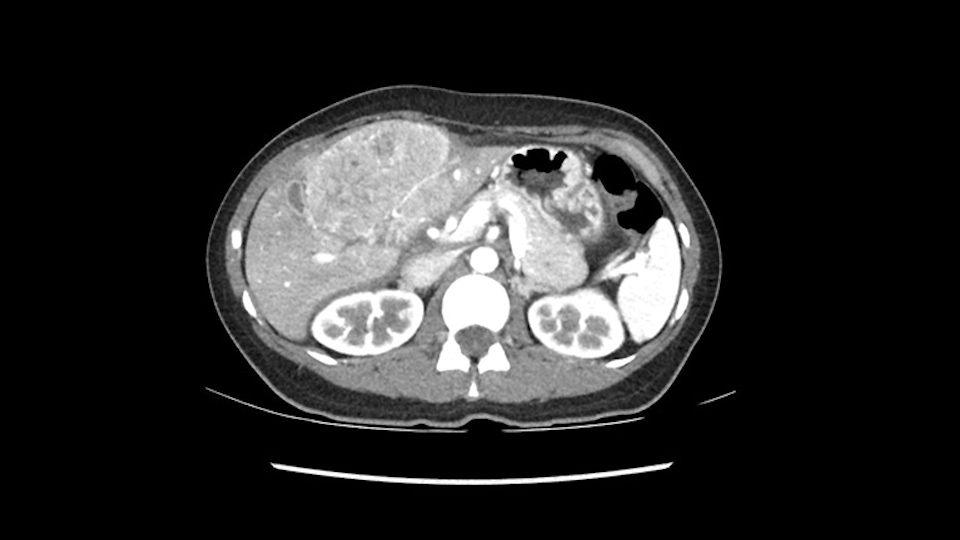

Now let’s look at some specific anatomical points for planning this surgery. First thing you see when you see a left hemihepatectomy is that where is the left portal vein and the right portal vein branching? And what is the stump of the left portal vein available for you for ligation? In this particular case, you’ll find that there’s overhanging of the tumor but left portal vein pedicle is sufficiently available for us for ligation.

The cava however is again displaced by this well encapsulated mass, so I would expect that I should be able to lift out of the cava with some moment of careful dissection and the cava is not infiltrated by this tumor. Most of the tumor is below the portal plane and the hepatic-venous vein is completely free. You have the left and the middle hepatic vein joining together and opening up. The right hepatic vein is as usual. All the superior segments of the liver are intact so we do not expect any major problem in this particular case as far as the venous outflow is concerned. So this is about the preoperative planning as far as this case is concerned.

The next step would obviously be the left hepatic vein mobilization. Once you lift the left lateral segment up, and you mobilize from the caudate lobe, you’ll find that you need to identify [Arantius’ canal] and ligate [Arantius’ canal], then only the left hepatic vein comes into view at the apex of the caudate lobe. In this particular case, because the hepatic venous plane is intact and its pretty free, it’s quite easy to ligate the left hepatic vein and staple it off. That would complete the devascularization of the tumor.